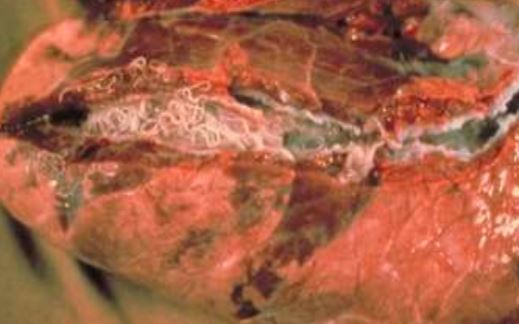

These worms were found in the lung of a cow. What species do you suspect?

Dictyocaulus spp.

Whenever you see a mass of worms in the bronchi of a ruminant, you should think Dictyocaulus.

Because this is a cow, the species is probably Dictyocaulus viviparous